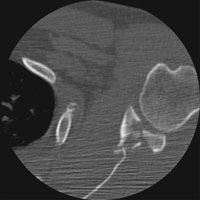

DGlenoid Fracture |

Glenoid fractures are usually the result of blunt trauma to the upper extremity. Subtle fractures can be difficult to detect on conventional radiographs; CT may be required for full diagnosis. A special glenoid fracture is termed the Bankart fracture. This consists of fracture of the inferior lip of the glenoid during anterior shoulder dislocation.